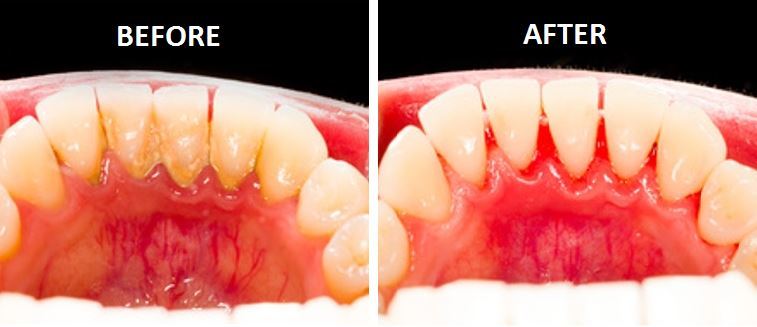

맘스키즈에서 정기검진 후 불소치료를 하는 친구들 중에는 원할 때마다 치석을 제거해주는 분들도 계시고, 아랫니 앞니 안쪽 부분만 특별히 칫솔질을 하지 않아서 스케일링을 받는 분들도 계십니다. 하지만 아이들은 전반적으로 성인과 마찬가지로 많은 부분을 발달시킵니다. 이유는 무엇입니까?

유치가 치석을 형성할 때 치석이 가장 자주 형성되는 곳은 어디입니까? 대부분의 일차 치석은 아래 앞니 안쪽에 형성됩니다. 아래쪽 안쪽 치아는 침샘이 분비되는 곳으로, 충치가 생기지 않도록 쉽게 청소할 수 있는 부위입니다. 하지만 영구치아가 잘 낫지 않는 부위이기 때문에 칫솔을 세워서 장시간 문지르는 것이 필요합니다.

양치질로는 치석을 제거할 수 없나요? 마개는 칫솔질로 쉽게 제거할 수 있지만, 이미 결석으로 굳어진 치석은 치과에서 기계적으로 제거해야 합니다.

아기 치아에 치석이 있어서 치석을 제거해야 한다면 실제로는 양치질을 제대로 하지 않는 것입니다. 치석은 한번 형성되면 제거한 후에 다시 생길 가능성이 높습니다. 아이가 양치질을 한 후에는 부모가 철저하게 양치질을 마무리해야 합니다! 꼭 해보세요~~^^